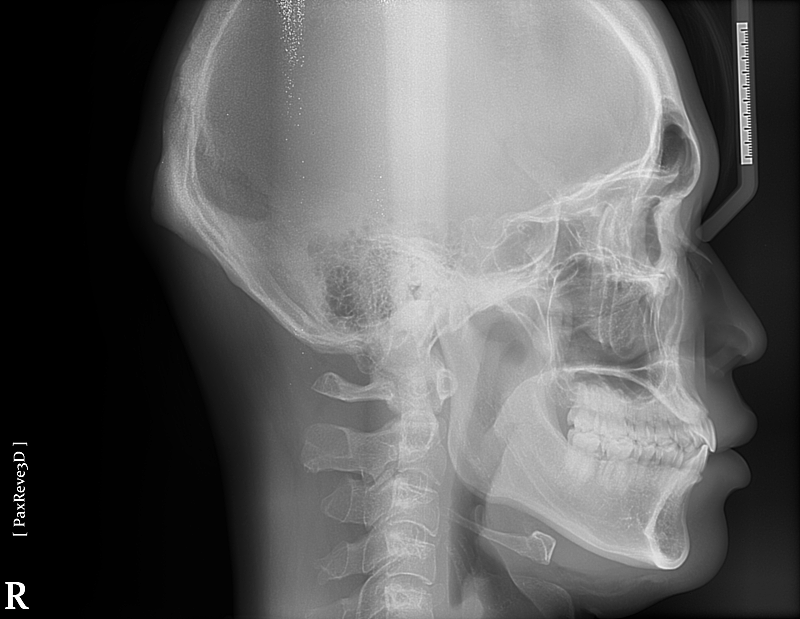

턱이 나오거나 돌출된건가요??

1.제 턱이 정상사람 보다 앞으로 나오거나 돌출된 건가요???

2.이런 얼굴은 발치교정하면 얼굴이 길어보일 수 있나요????

• 2번 째 사진

1. 말씀하신 것은 연조직까지 같이 평가해야 합니다. 골격상에는 앞으로 튀어나왔다고 하더라도 연조직에서 그렇게 보이지 않을 수 있습니다. 또한 계측된 값들이 필요하며 교정치과 방문 후 수치를 알아보시길 바랍니다.

2. 발치 교정을 통해 얼굴이 길어질지는 안모에 대한 자료도 필요합니다.

사진상으로는 아래턱이 크게 문제가 있어 보이진 않습니다. 궁금하시다면 교정진단을 통해서 정상범위에서 얼마만큼 차이가 있는지 확인할수 있습니다.